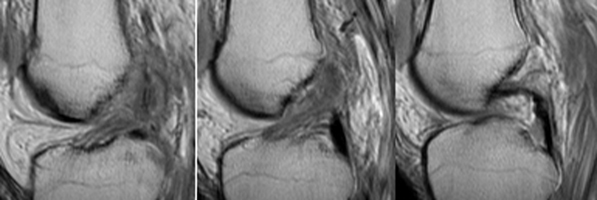

- Click on the image for a larger versionBSagittal MRI. This sequence of images of the knee shows disruption of the ACL.